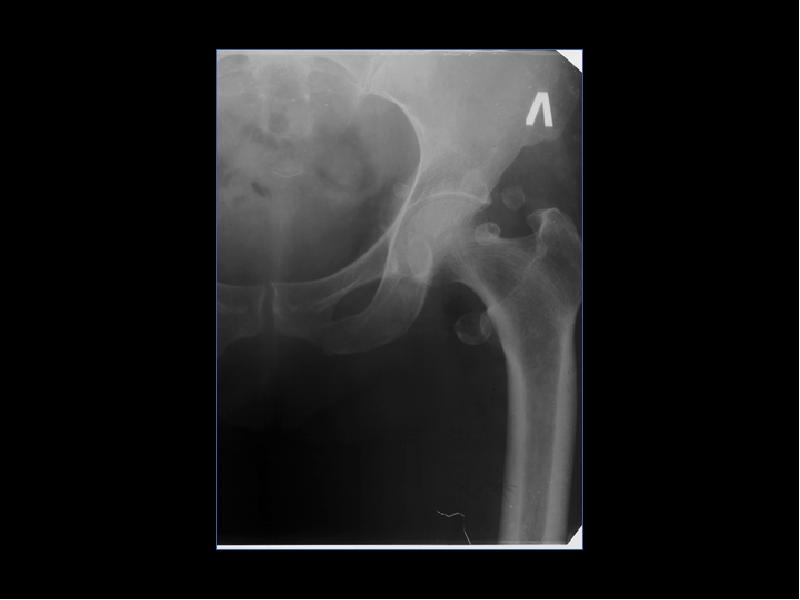

Лучевая диагностика доброкачественных